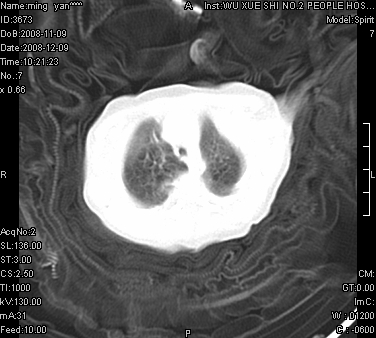

女.30天.咳嗽.喘3天.系三胞胎

考虑右肺下叶先天性肺囊肿,不除外合并右中叶肺发育不全

伴双肺感染

考虑右肺下叶先天性多发性肺囊肿可能。

考虑右肺下叶肺囊肿伴感染,右中叶节段实变或发育不全

这是一个先天性囊性腺瘤样畸形(congenital cystic adenomatid malformation,ccam),属于先天性肺发育异常,最近国外文献重新命名为先天性肺气道畸形(congenital pulmonary airway malformation,cpam),根据发生部位和畸形组织与气管、支气管的关系分成五型。本病以1岁以下婴儿多见,男性多于女性。病因为终末呼吸单元的异常增殖,形成多囊状结构。国内根据影响和病理表现分三型:ⅰ型为单个或多个大囊肿,直径大于2cm;ⅱ型为多个小囊肿,直径小于2cm;ⅲ型为大的非囊肿性病变,但显微镜下观察可见肿块由多发小囊组成(直径小于2mm)。本病可发生于肺内任何一部分,单侧肺占95%,中叶病变相对较少。